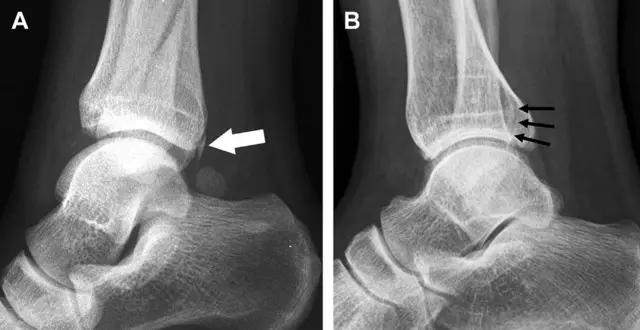

16 胫骨后踝骨折

涉及到三角韧带和外侧副韧带(LCL)的复杂性骨折常常不难发现,尤其是存在表面软组织肿胀时。然而,后胫腓韧带牵拉引起的胫骨后踝骨折则很难发现。这些骨折大小不一(图 2),却很重要,因为他们常与胫骨远端螺旋骨折有关,或者是三踝骨折的一部分。

图 2 胫骨后踝骨折。A 侧位片示来源于胫骨后踝的一个小骨折碎片(箭头),因踝部扭伤导致;B 另一位跖屈损伤的患者,侧位片示一个大骨折块(箭头)